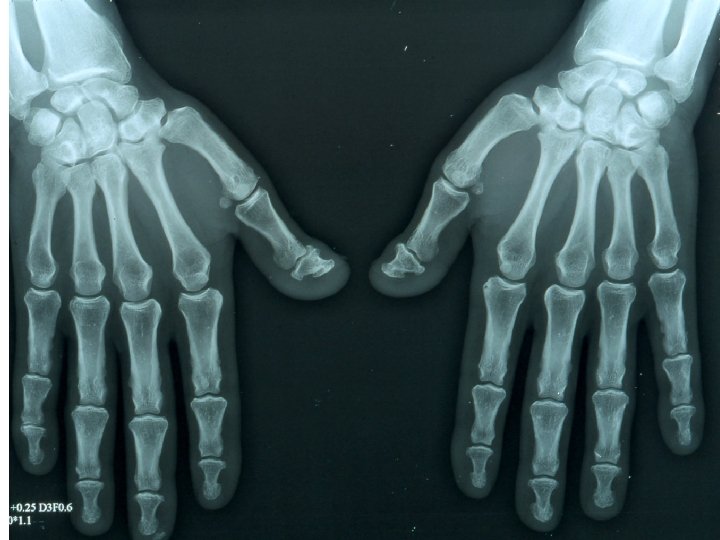

Une femme de 40 ans décrit des douleurs des chevilles apparues en décembre 2009, insuffisamment soulagées par la prise d’antalgiques mais répondant bien aux AINS. ATCD : HTA traitée par Avlocardyl, une grossesse, pas d’antécédent de faussecouche, pas d’antécédent thromboembolique. Vous la voyez pour la 1ère fois début février 2010 car sont apparues secondairement des douleurs très invalidantes du genou gauche, du poignet droit et du coude droit. L’examen clinique montre encore un empâtement des chevilles, révèle des douleurs à la pression du poignet droit et réveille des douleurs du coude droit à la mobilisation. L’auscultation cardio-pulmonaire est par ailleurs normale, la pression artérielle est à 11/6, le poids est à 71 kg pour 1 m 65. Vous réalisez des radiographies standard : chevilles, genoux, mains et poignets qui sont sensiblement normales ainsi qu’un bilan biologique: hémoglobine : 13, 8 g/d. L, globules blancs 5 400/mm 3, plaquettes 195 000/mm 3, VS : 8 mm/h, CRP : 3 mg/L.

Erosions vues en IRM au cours d’une PR